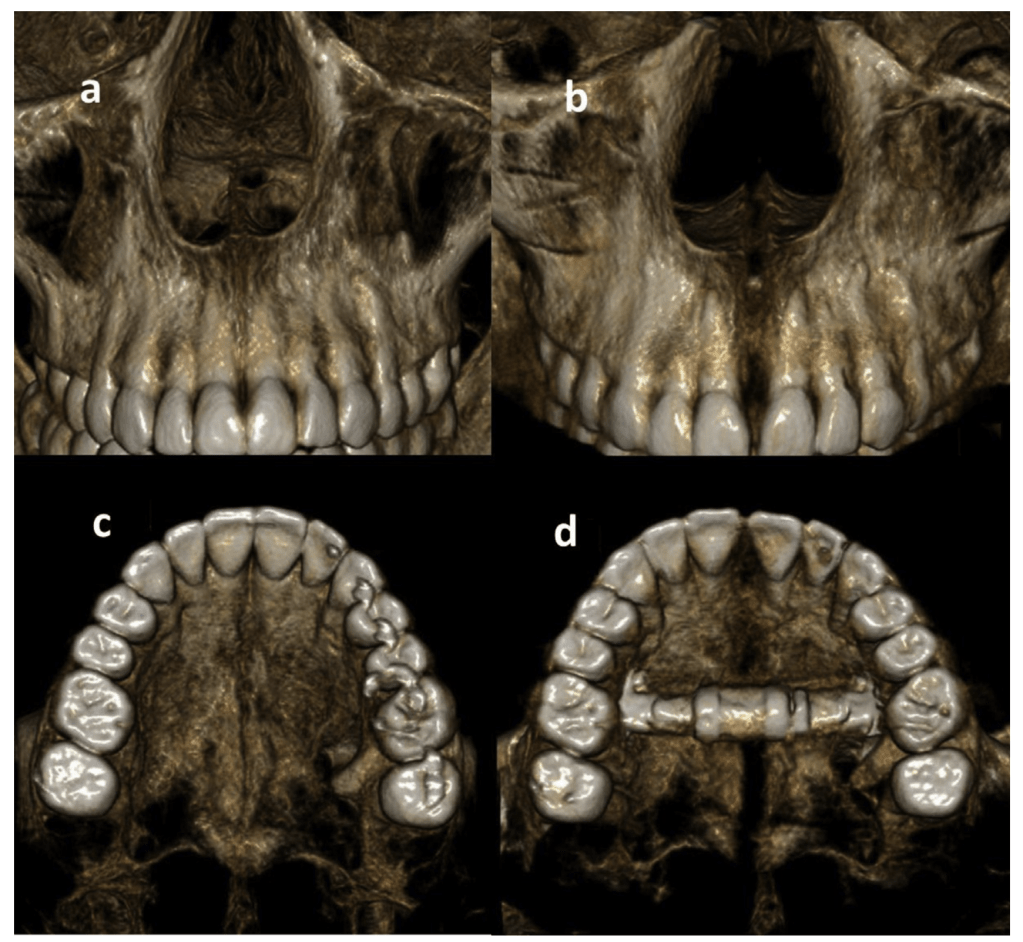

MARPE (Mini-screw or Mini-implant Assisted Rapid Palatal Expansion), also known as MSE (Maxillary Skeletal Expansion) is an appliance positioned and anchored directly on the maxillary bone, bringing horizontal expansion forces close to the midpalatal suture. There are different variations of the appliance, some with connecting arms attached to the teeth, others without teeth anchorage. When the teeth anchorage is present, the appliance is referred to as hybrid or tooth-bone-borne appliance. Studies have shown that arms prevent the distal rotation of the teeth when the appliance is activated.

While literature on the procedure is missing, the common understanding is that EASE sits in between MARPE and SARPE. A transpalatal distractor (TPD) with footplates stabilized with a screw is placed in the palate and the expansion is facilitated by achieving pterygomaxillary separation with a piezoelectric blade. A midpalatal osteotomy is also performed to reduce the midpalatal suture resistance. The result is a more parallel expansion of the midpalatal suture, increased nasal volume and reduced diastema.

SARPE (Surgically-Assisted Rapid Palatal Expansion), also known as DOME (Distraction Osteogenesis Maxillary Expansion), is a combination of both Oral and Maxillofacial Surgery and Orthodontics that is done to achieve a more predictable maxillary skeletal expansion in adults. It combines a maxillary expander anchored to the palate by mini-implants with minimally invasive LeFort I osteotomies. Midpalatal osteotomy is also performed to break the inter-maxillary suture. Usually, the pterygoid plates are not involved in this procedure. However certain surgeon might decide to separate the plates. The separation is called pterygomaxillary disjunction, PMD.